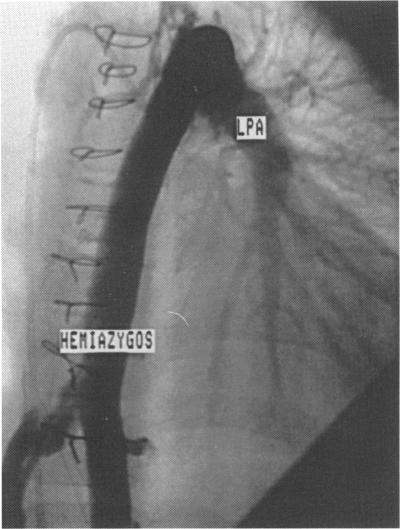

Postoperative angiography in case 1 showed a remnant of a left inferior vena cava draining to the atrium to have become grossly dilated causing cyanosis, which resolved after redirection of this vessel and of the hepatic veins into the right pulmonary artery with an intra-atrial baffle. Cyanosis in case 2 was caused by intra-hepatic shunting to a hepatic vein draining to the left of the intra-atrial baffle. The diagnosis was made at necropsy, being overlooked on postoperative angiography. Repeat angiography in case 3 showed progressive dilatation of a small left superior vena cava to coronary sinus. Test occlusion with a view to embolisation revealed hitherto an undemonstrated hemiazygos continuation of inferior caval to brachiocephalic vein. The patient underwent surgical ligation of these two venous channels.

病例1术后血管造影显示引流至心房的左下腔静脉残余部分明显扩张,导致发绀,在通过心房内挡板将该血管及肝静脉改道至右肺动脉后发绀消失。病例2的发绀是由肝内分流至引流至心房内挡板左侧的肝静脉所致。该诊断在尸检时才得以明确,术后血管造影时被漏诊。病例3再次血管造影显示左无名静脉至冠状窦的一小段左头臂静脉逐渐扩张。为栓塞进行的试验性闭塞显示出此前未发现的下腔静脉至头臂静脉的半奇静脉延续。该患者接受了这两条静脉通道的手术结扎。